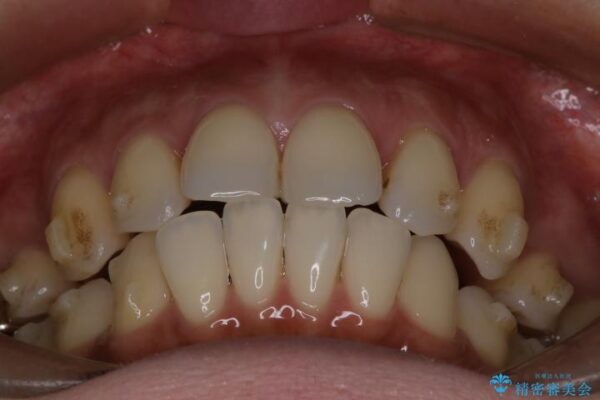

上の前歯の突出感を気にして来院された患者様です。

治療前

• 上顎前歯の突出を軽減 インビザラインによる抜歯矯正 治療前画像